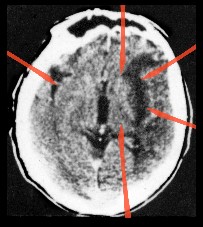

Der erste entdeckte „Hamersche Herd“

Bereits 1982 gelang es mir – also ein Jahr nach der Entdeckung der Germanischen Heilkunde (damals noch „Eiserne Regel des Krebs“) – schon prospektiv einen Hamerschen Herd (HH) riesigen Ausmaßes bei einem Patienten mit Revierkonflikt in der Heilungsphase und Herzinfarktgeschehen in der epileptoiden Krise zu finden.

Von da ab wusste ich, dass es keine Hirntumoren gab, sondern dass diese Phänomene alle im Zusammenhang mit der Lösungsphase eines biologischen Konfliktgeschehens stehen mussten.

Der Patient, zu dem diese Bilder gehören, war der allererste, bei dem ich prospektiv einen später sog. „Hamerschen Herd“ suchte und auch fand.